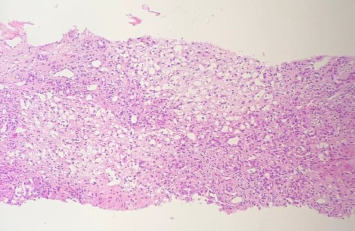

背景:几种自身免疫性疾病,如自身免疫性肝炎(AIH),可在COVID-19感染或疫苗接种后出现或失代偿;然而,缺乏关于同时感染COVID-19和自身免疫性疾病的管理数据。病例总结:本文报告1例9岁男童,皮肤和巩膜黄变,肝功能检查异常,随后出现SARS-CoV-2 qRT-PCR阳性和进行性双氧体减少症。在对皮质类固醇缺乏反应后,静脉注射免疫球蛋白(IVIg),观察到肝酶、总胆红素和直接胆红素的下降。结果与讨论:本病例说明了IVIg如何显著改善了SARS-CoV-2检测qRT-PCR阳性患者的AIH症状。我们希望我们的报告能够鼓励对COVID-19合并AIH治疗方法的进一步研究。

Background: Several autoimmune diseases, such as autoimmune hepatitis (AIH), can arise or become decompensated following COVID-19 infection or vaccination; however, there is a lack of data regarding the management of concurrent COVID-19 infection and autoimmune diseases. Case Summary: In this paper, we present a case of a 9-year-old boy with yellowish discoloration of the skin and sclera, abnormal liver function test, followed by positive qRT-PCR for SARS-CoV-2 and progressive bicytopenia. After a lack of response to corticosteroids, intravenous immune globulin (IVIg) was administrated and a decline in liver enzymes, total bilirubin, and direct bilirubin was observed. Result and Discussion: This case illustrates how IVIg significantly improved the AIH symptoms in the patient with positive qRT-PCR for the SARS-CoV-2 test. We hope our report encourages further research on therapeutic approaches for AIH concomitant with COVID-19.